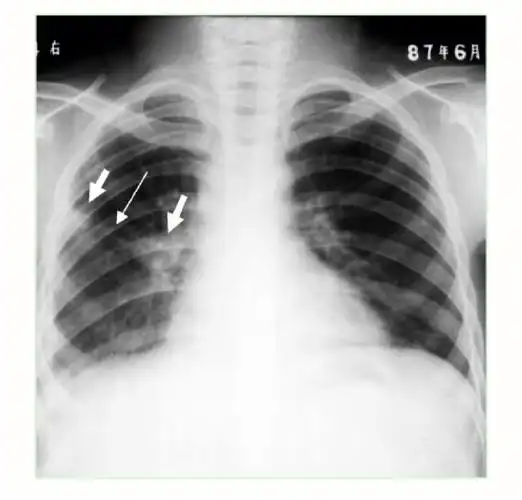

经颈前外侧入路切除颈4/5哑铃状神经鞘瘤一例(脊柱脊髓系列十二)

上海长征医院蒋磊副教授颈椎管内外哑铃型神经鞘瘤的手术治疗

经颈前外侧椎间孔入路切除颈椎哑铃型肿瘤的手术思考